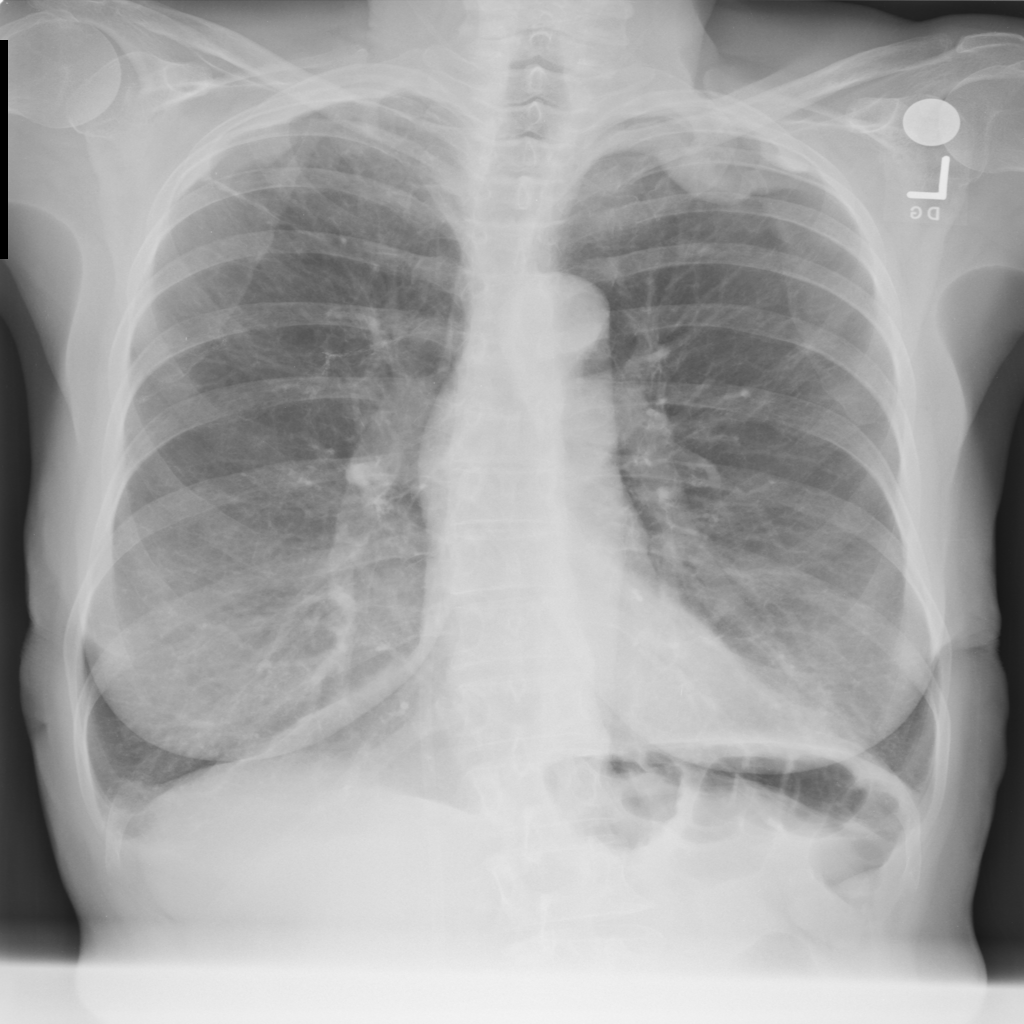

PAT-E066 · IMG-010Fibrosis

PAT-E066 · IMG-010

PA